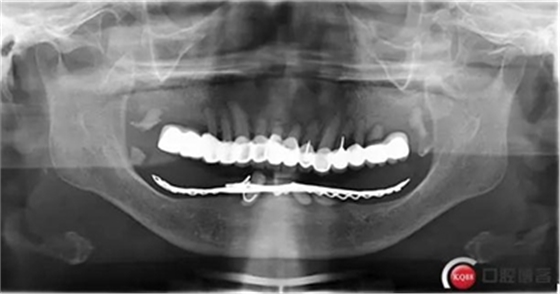

全過程約70日。因下牙槽骨較低,事前拍全景片。至今完成修復3個月,咀嚼效果良好。